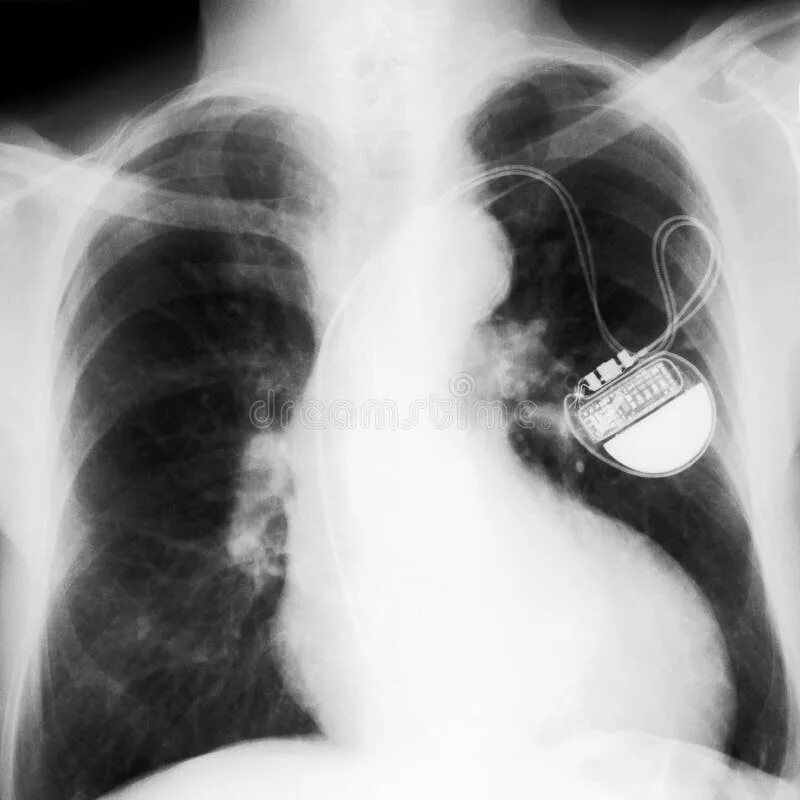

Как делают операцию кардиостимулятор